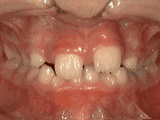

牙列拥挤

丨症状表现

牙齿过多,牙槽骨过窄,使牙齿没有足够空间生长就会造成牙齿排列不齐,需根据情况判断是否拔牙。